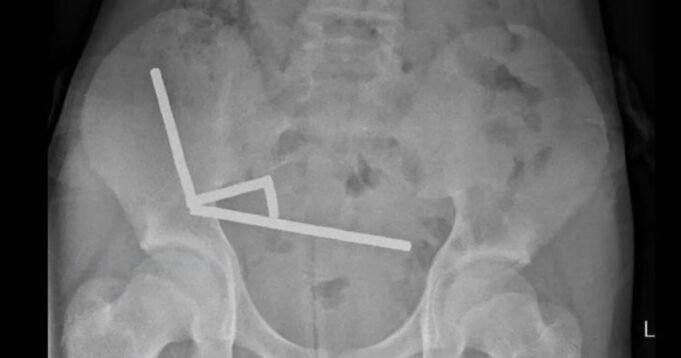

Después de cuatro días de dolor de estómago, el niño de 13 años ingresó en el hospital de Tauranga, en la Isla Norte de Nueva Zelanda, donde los médicos descubrieron que los imanes se habían unido para formar cuatro cadenas dentro de sus intestinos.

Los cirujanos extrajeron los imanes y extirparon partes de los intestinos dañados del niño, según un informe de los médicos del hospital. publicado el viernes en el New Zealand Medical Journal.

El niño, que no fue identificado en el informe, había ingerido «aproximadamente entre 80 y 100 imanes de neodimio de alta potencia de 5 x 2 mm» una semana antes de su hospitalización, dijeron los médicos. Fue dado de alta tras pasar ocho días en el hospital.